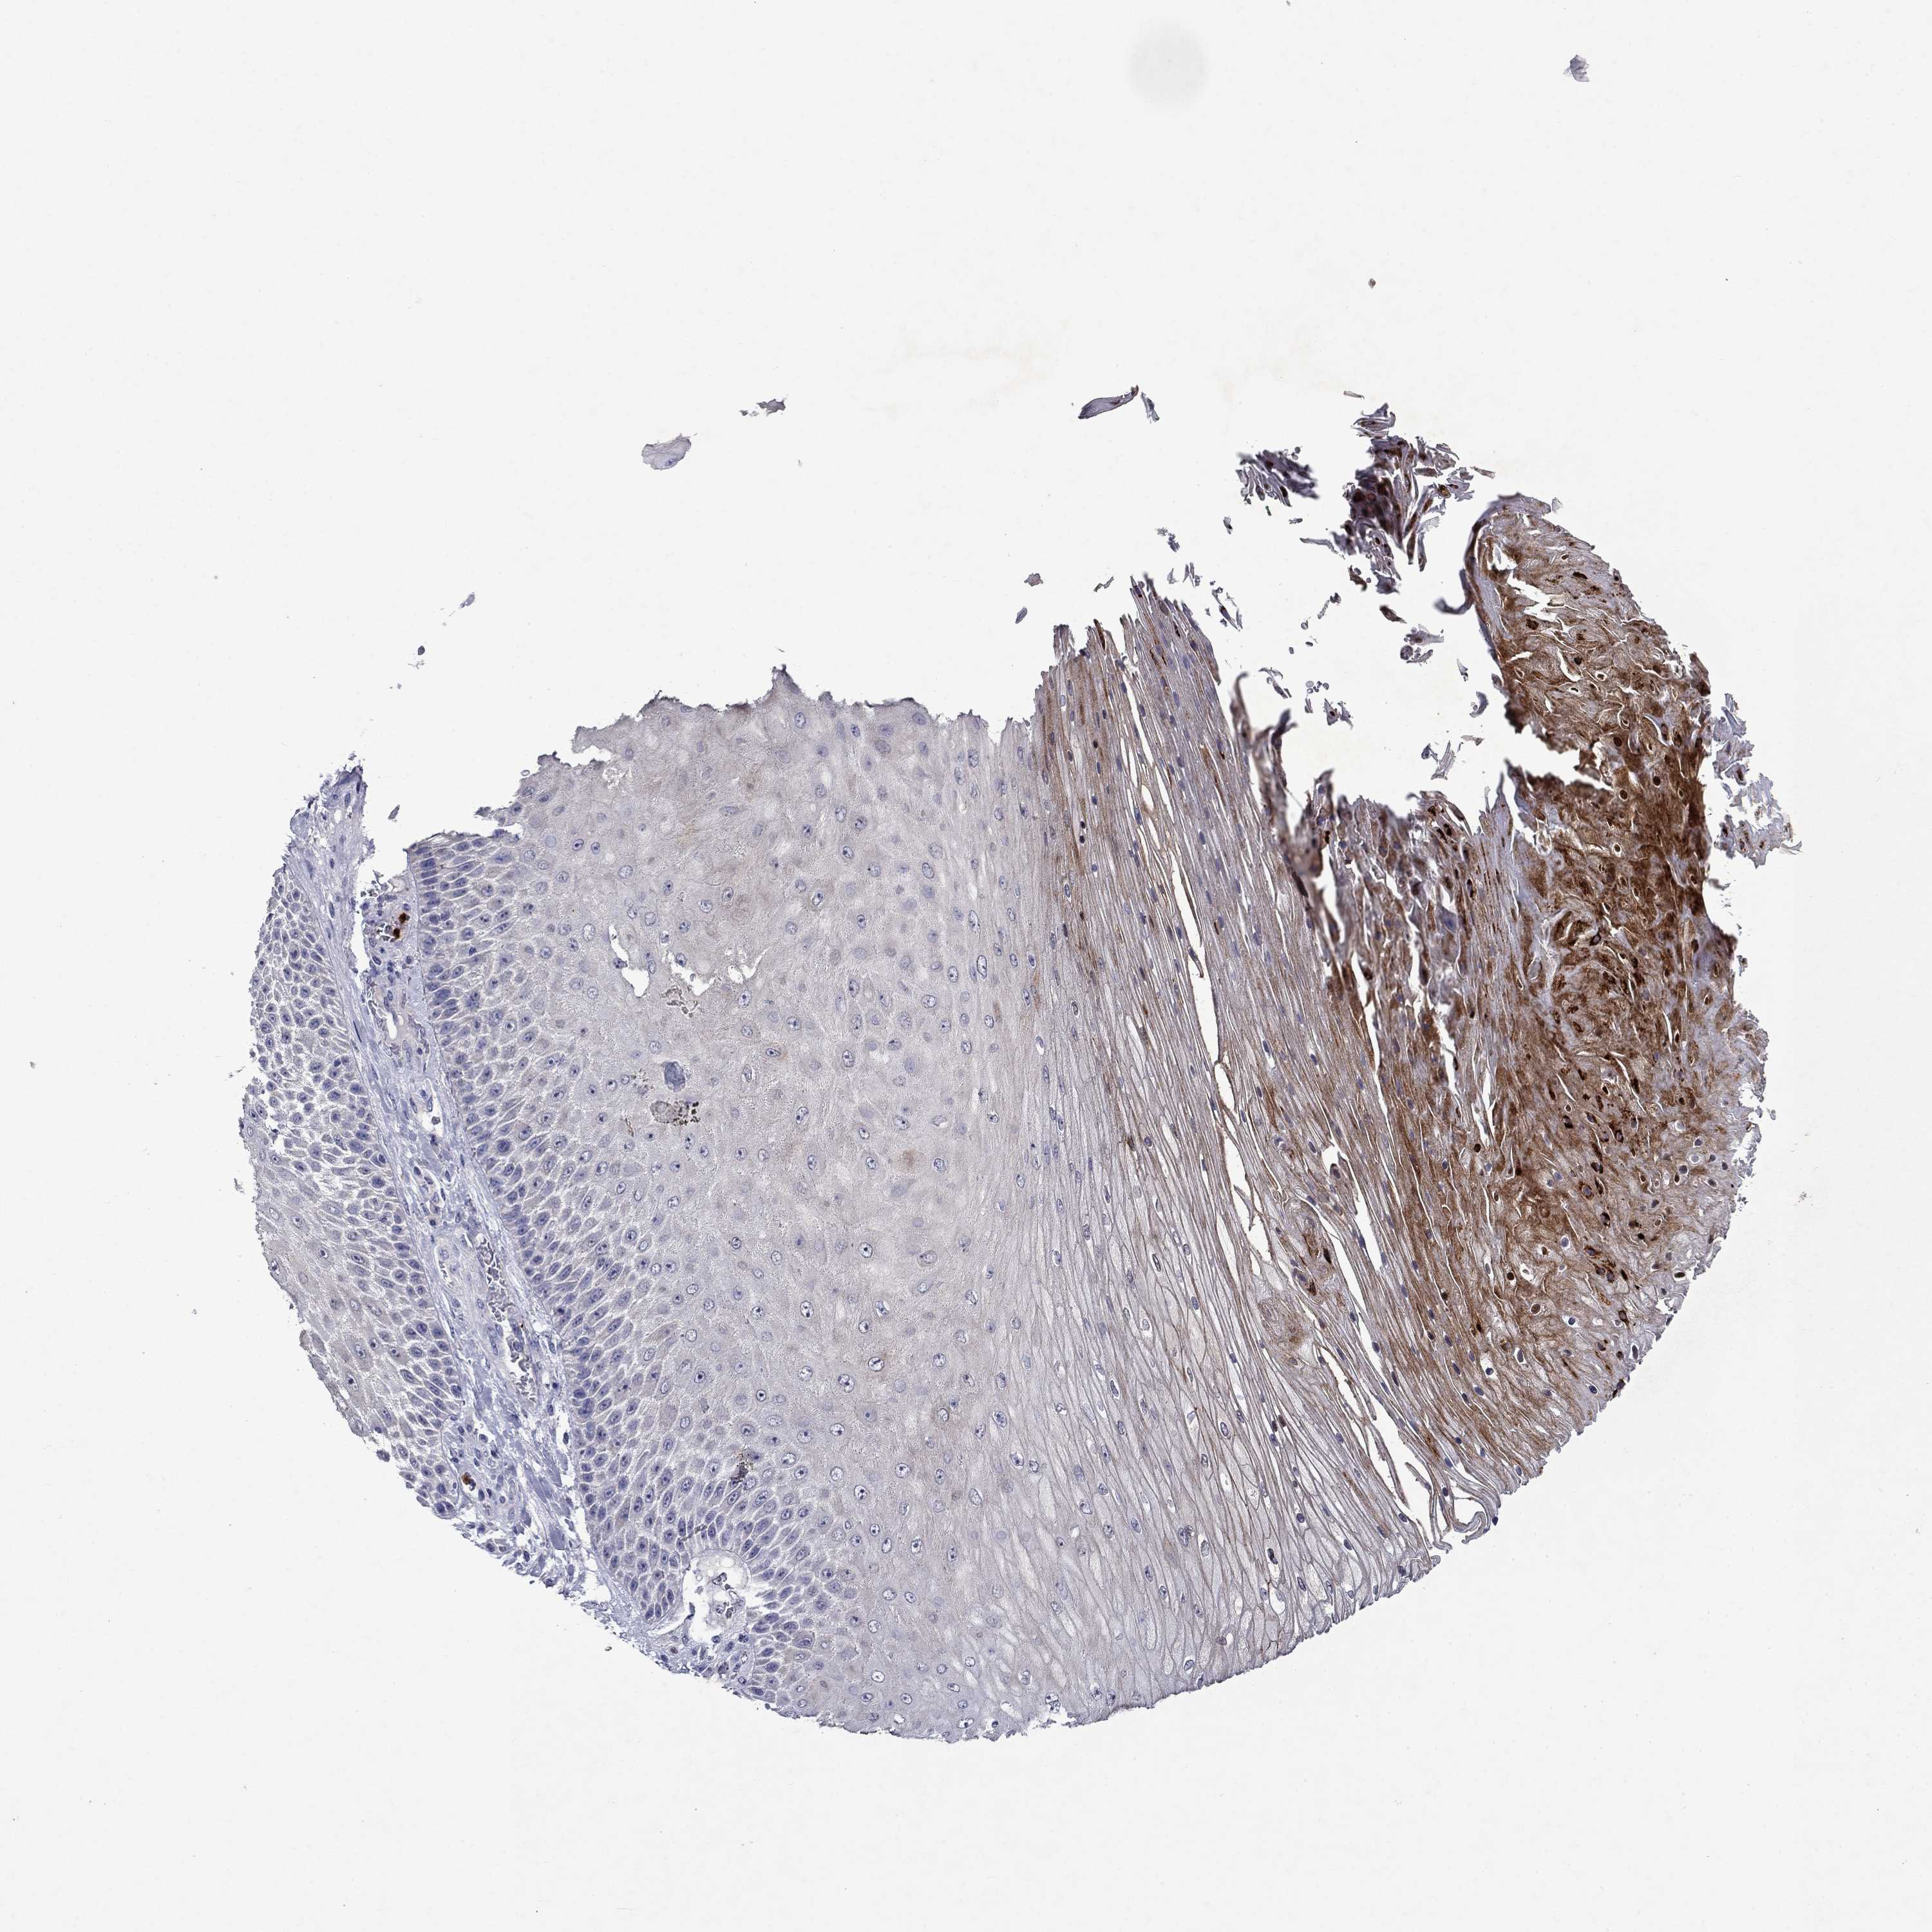

SKIN CANCER - Protein expressioni

A mouse-over function shows sample information and annotation data. Click on an image to view it in a full screen mode. Samples can be filtered based on level of antibody staining by selecting one or several of the following categories: high, medium, low and not detected. The assay and annotation is described here.

Antibody stainingi

Antibody staining in the annotated cell types in the current human tissue is reported as not detected, low, medium, or high, based on conventional immunohistochemistry profiling in selected tissues. This score is based on the combination of the staining intensity and fraction of stained cells.

Each image is clickable and will lead to virtual microscopy that enables deeper exploration of all samples and also displays staining intensity scores, fraction scores and subcellular localization as well as patient and tissue information for each sample.

Squamous cell carcinoma, metastatic, NOS